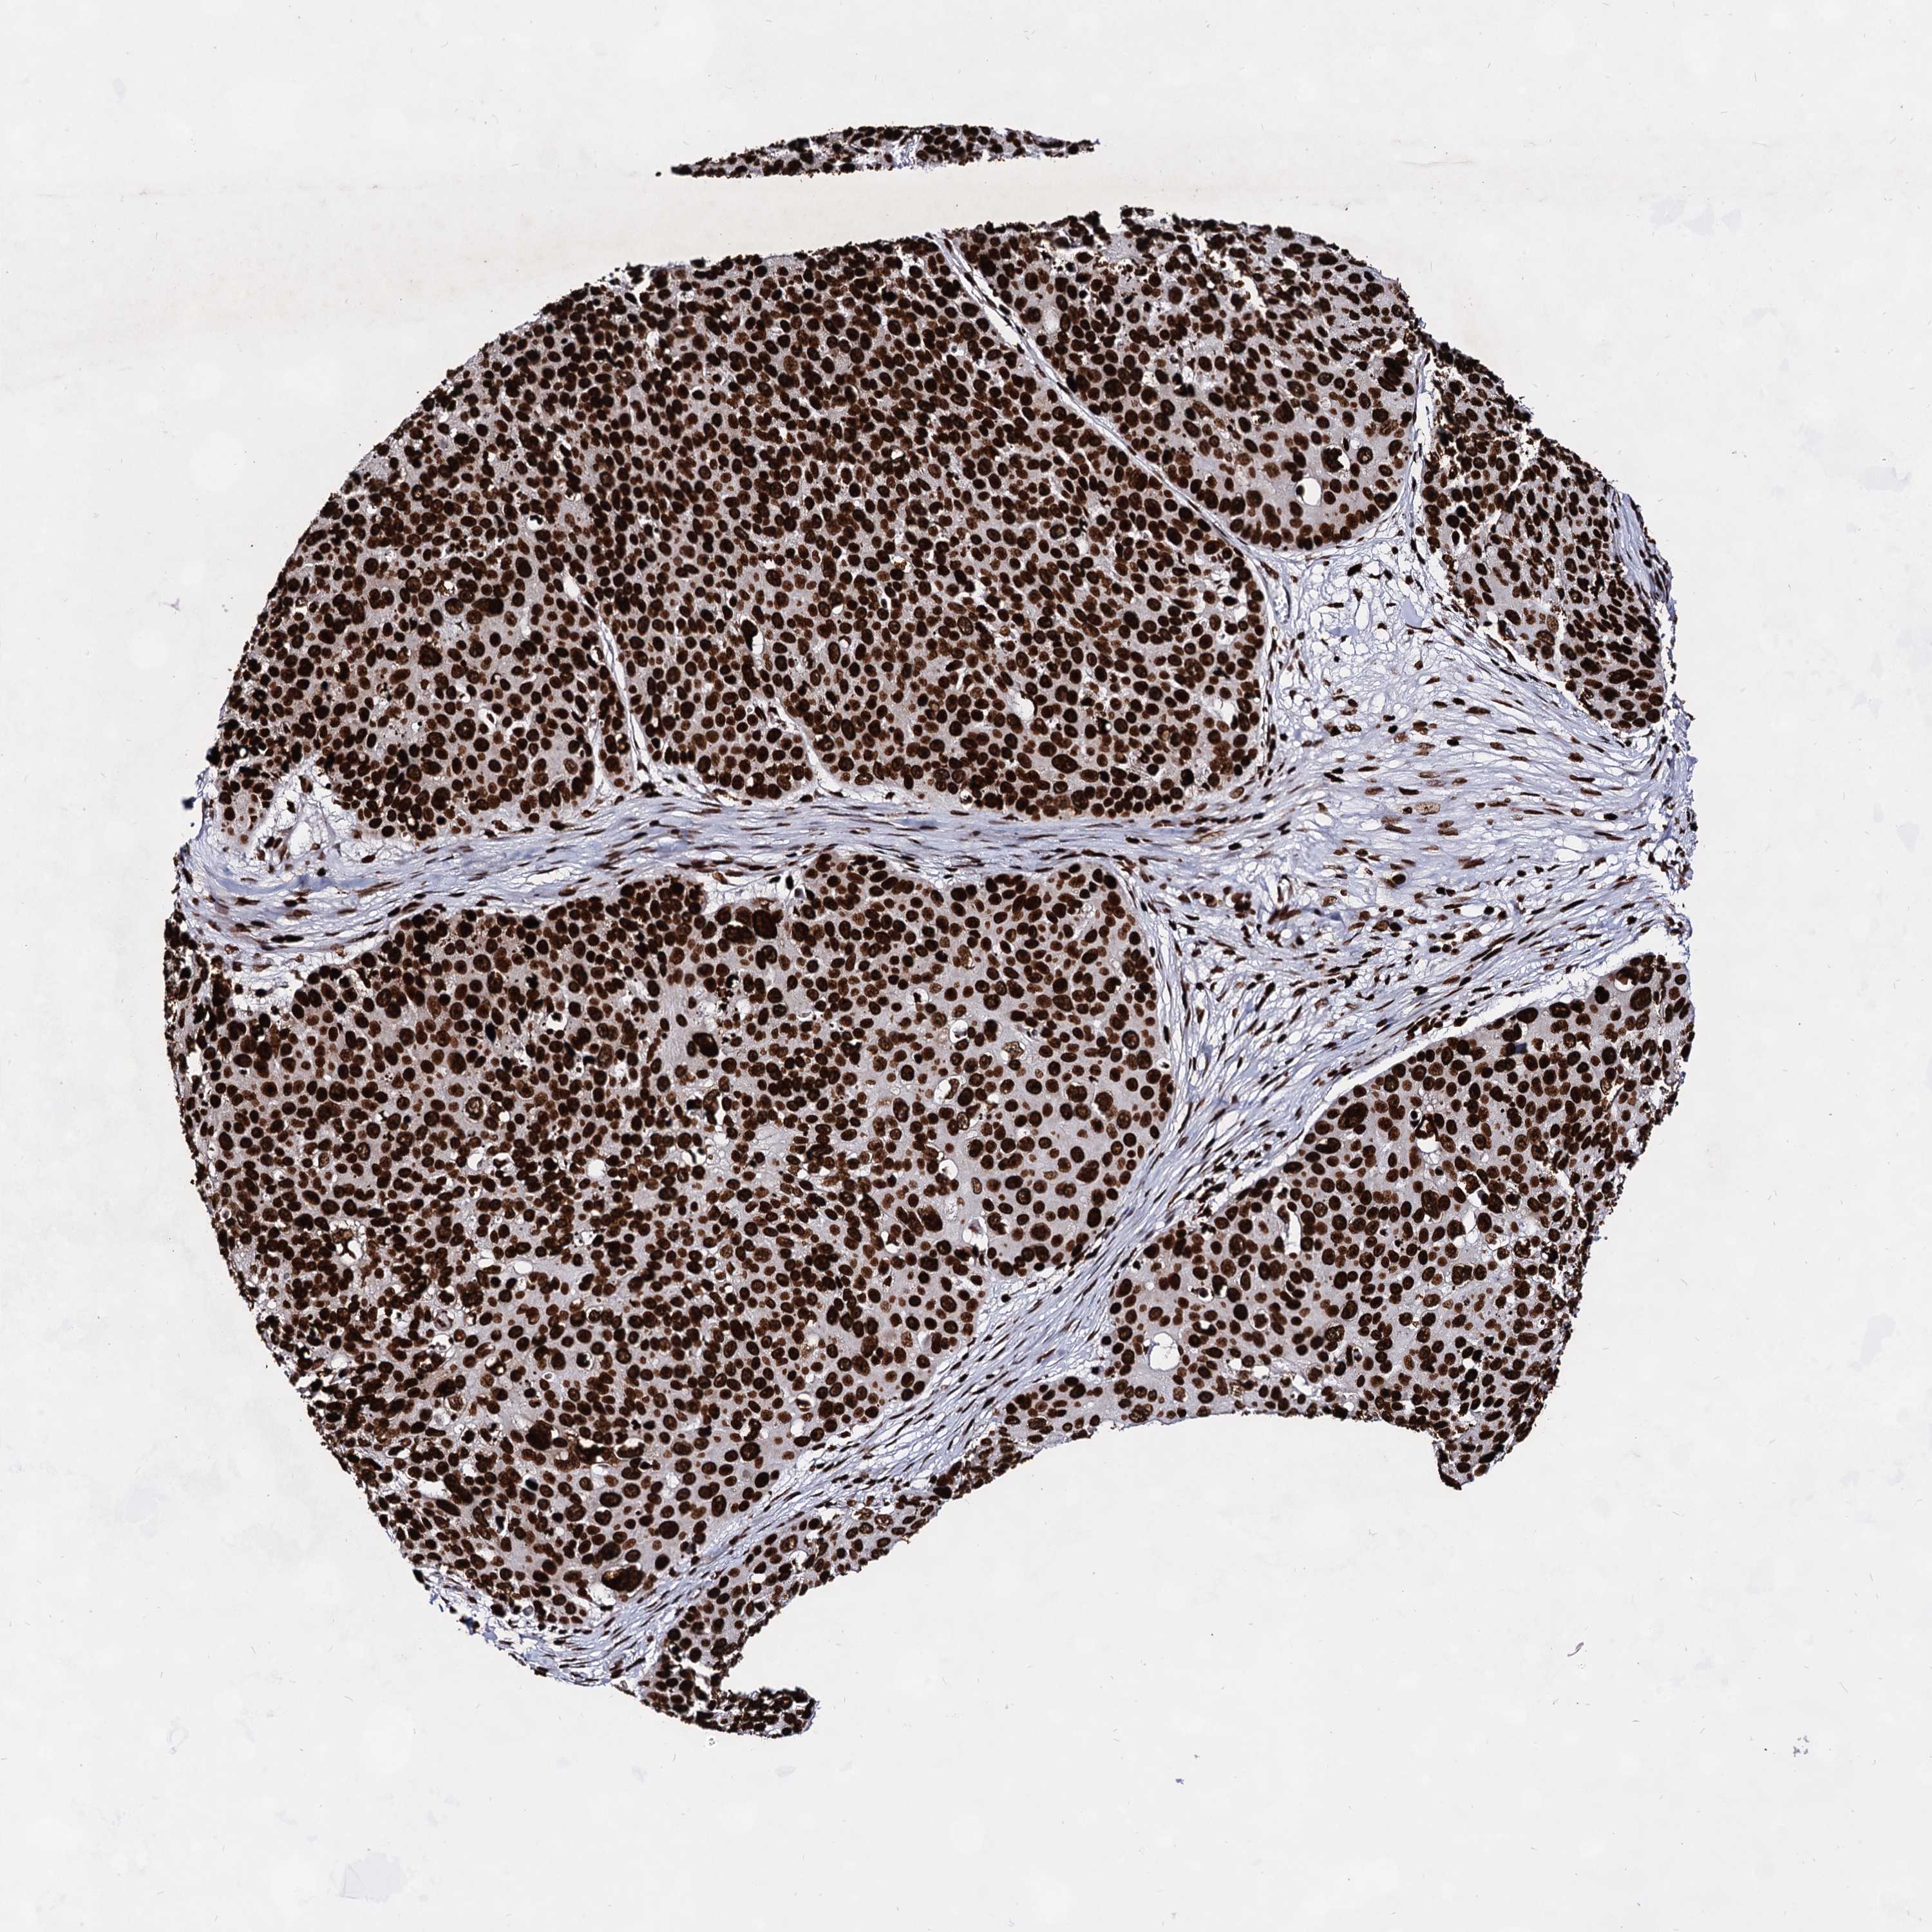

SKIN CANCER - Protein expressioni

A mouse-over function shows sample information and annotation data. Click on an image to view it in a full screen mode. Samples can be filtered based on level of antibody staining by selecting one or several of the following categories: high, medium, low and not detected. The assay and annotation is described here.

Each image is clickable and will lead to virtual microscopy that enables deeper exploration of all samples and also displays staining intensity scores, fraction scores and subcellular localization as well as patient and tissue information for each sample.

Antibody CAB037206

Staining

High

Intensity

Strong

Quantity

>75%

Location

Nuclear

Squamous cell carcinoma, NOS

Basal cell carcinoma

Squamous cell carcinoma, metastatic, NOS